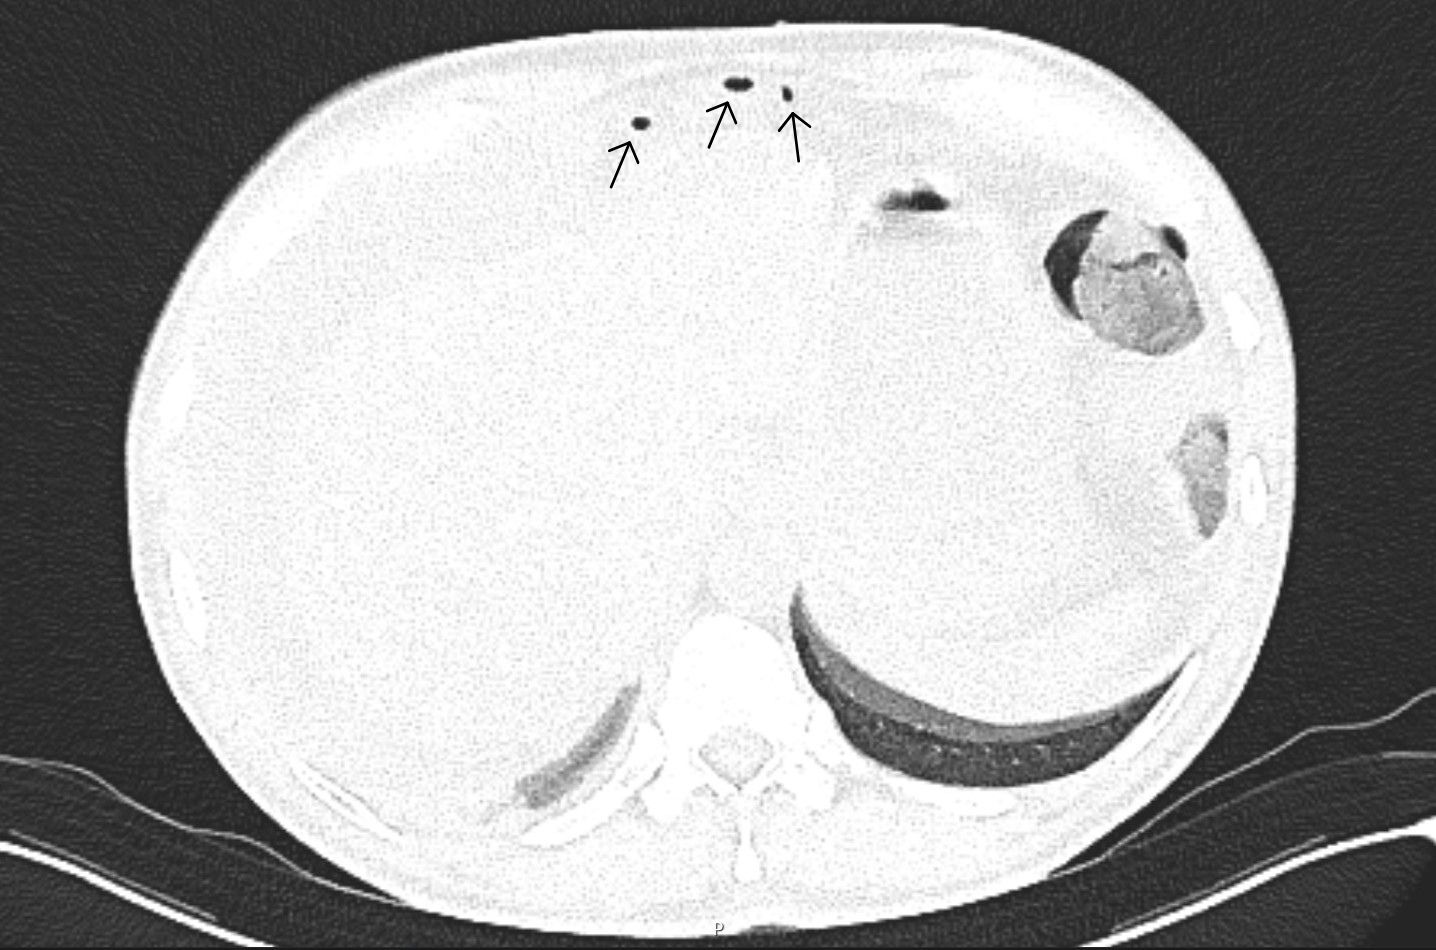

FIGURE 3: CT axial-plane (lung window setting) demonstrates extraluminal free gas within the anterior abdominal wall, in the prehepatic region (black arrows), indicative of gastrointestinal perforation.